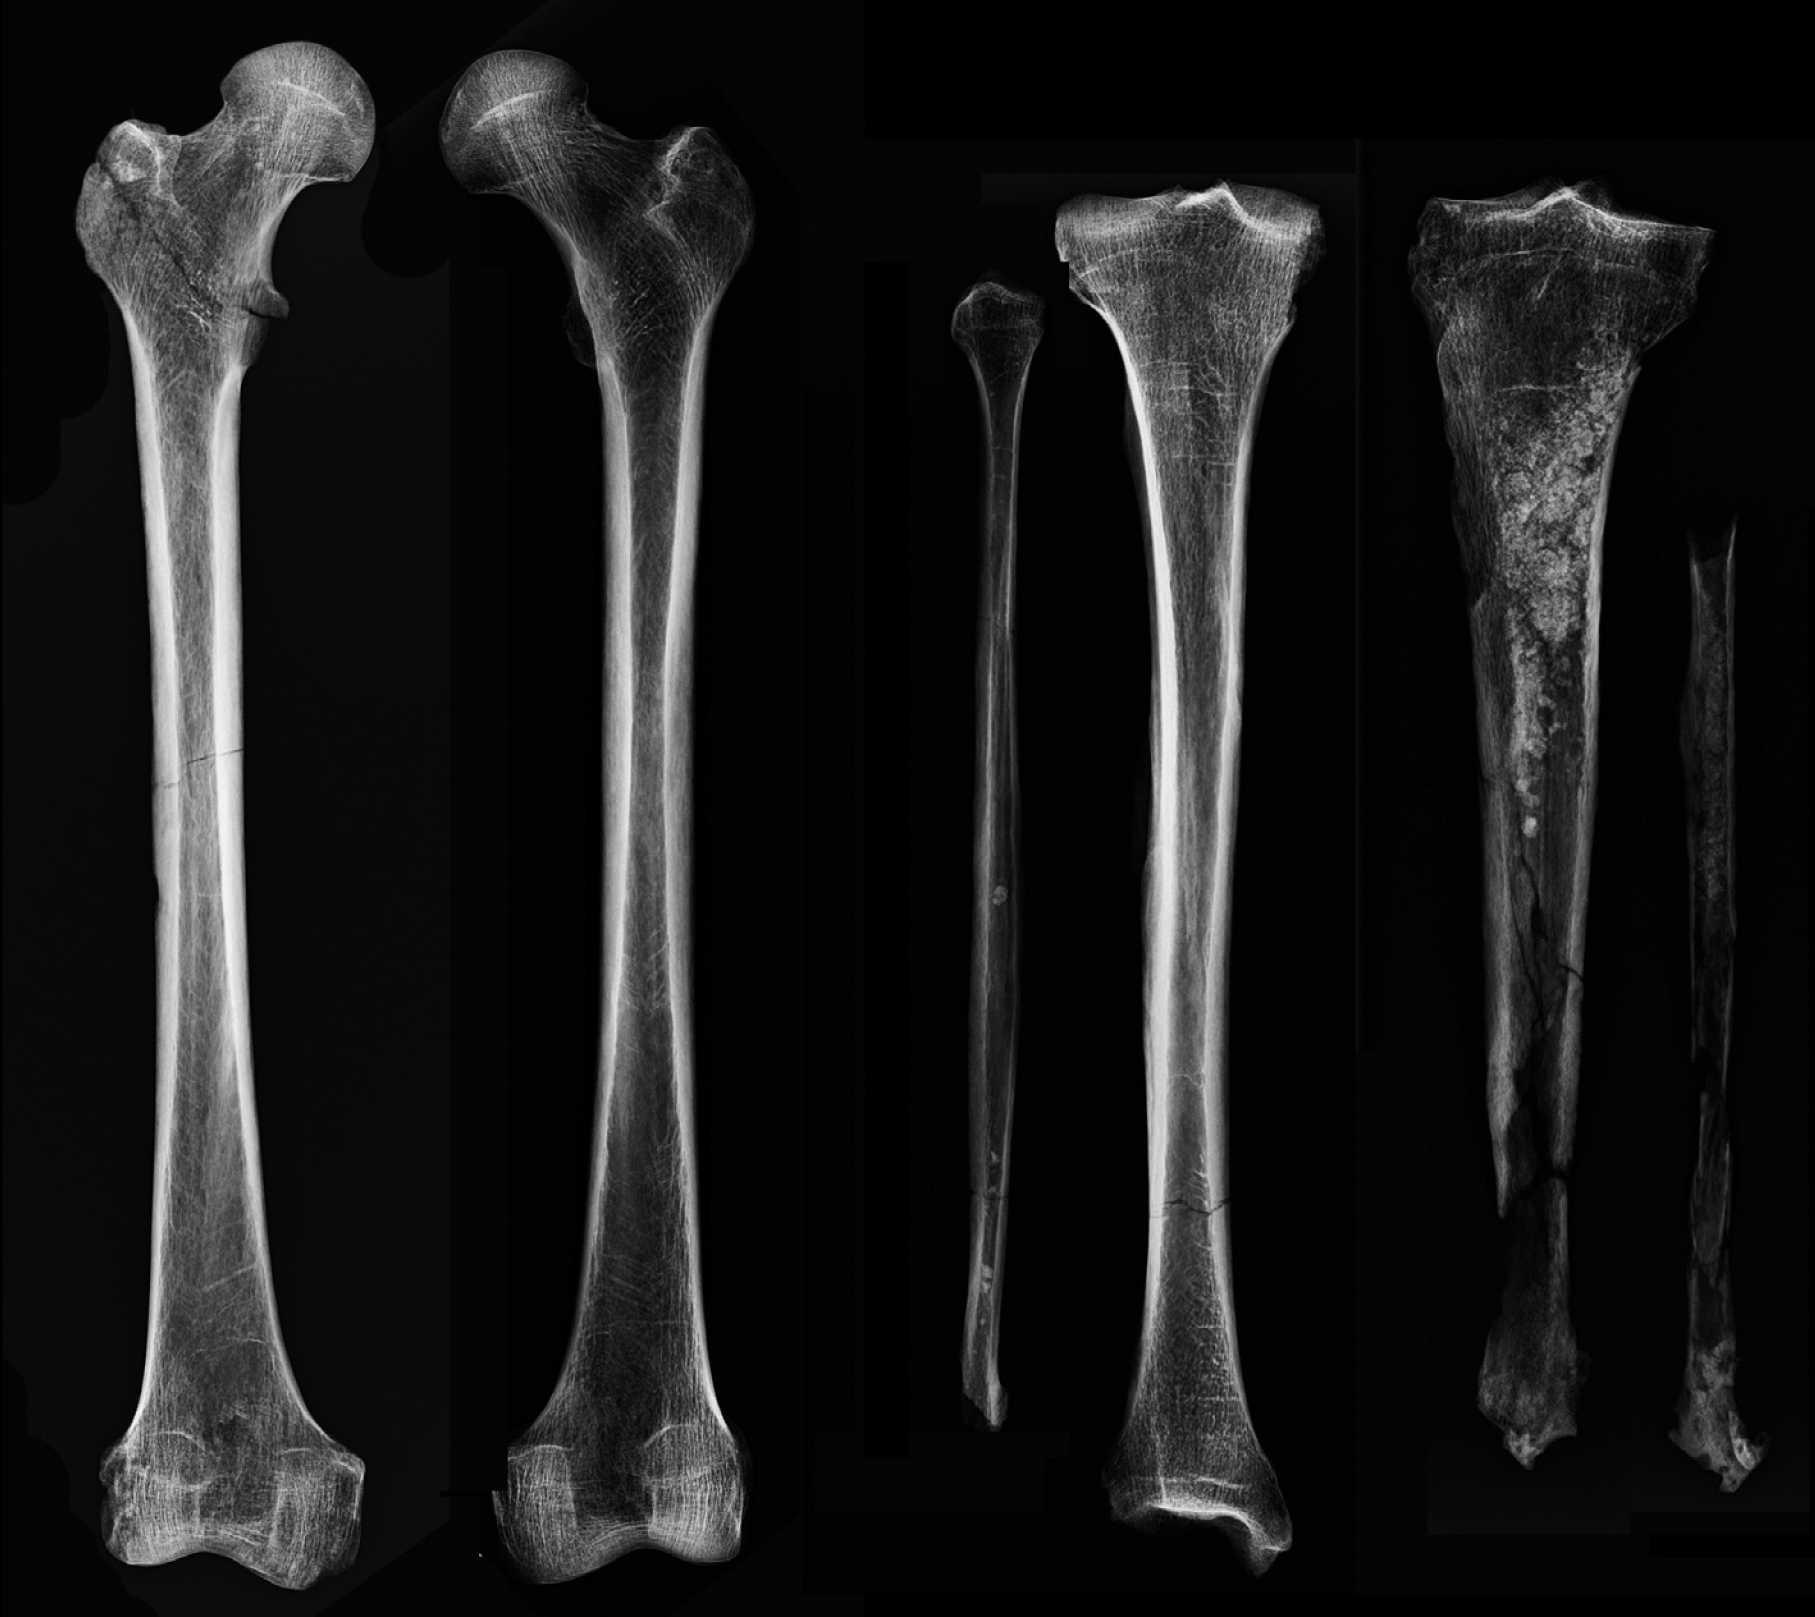

Selvittääkseen kuinka pitkään mies on elänyt amputaation jälkeen, Binder kollegoineen tutki röntgenkuvia. Luut kuvattiin myös tietokonetomografian avulla. Kuvantamismenetelmiä käytettiin, sillä silmin havaittavat leikkausjäljet voivat hävitä jopa kahdessa viikossa amputoinnin jälkeen. Röntgenkuvissa koko vasemman raajan luissa oli näkyvissä luun tiheyden muutoksia verrattuna oikeaan raajaan. Vasemmassa polvessa oli kuitenkin nivelrikkoa, joka kertoo siitä, että mies on käyttänyt jalkaansa myös amputaation jälkeen, todennäköisesti proteesin avustuksella.